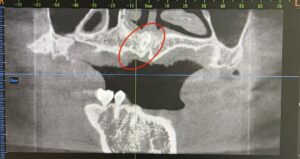

通常のレントゲンでは過剰歯の正確な位置や向き、周囲の神経・骨との関係までははっきりしませんでした😭

精密検査の一部CTデータを撮影することによって通常より多い歯(過剰歯)があごの骨の中に埋まっている状態が確認されました。

🦷過剰歯の正確な位置・深さ・方向が3Dで把握可能

🦷顎の骨や神経との距離も立体的に確認できる

🦷外科処置のリスク軽減や正確な治療計画につながる!

患者様のように埋伏過剰歯が骨の中に深く埋まっている場合でも、CTによって詳細な情報を得ることができます。